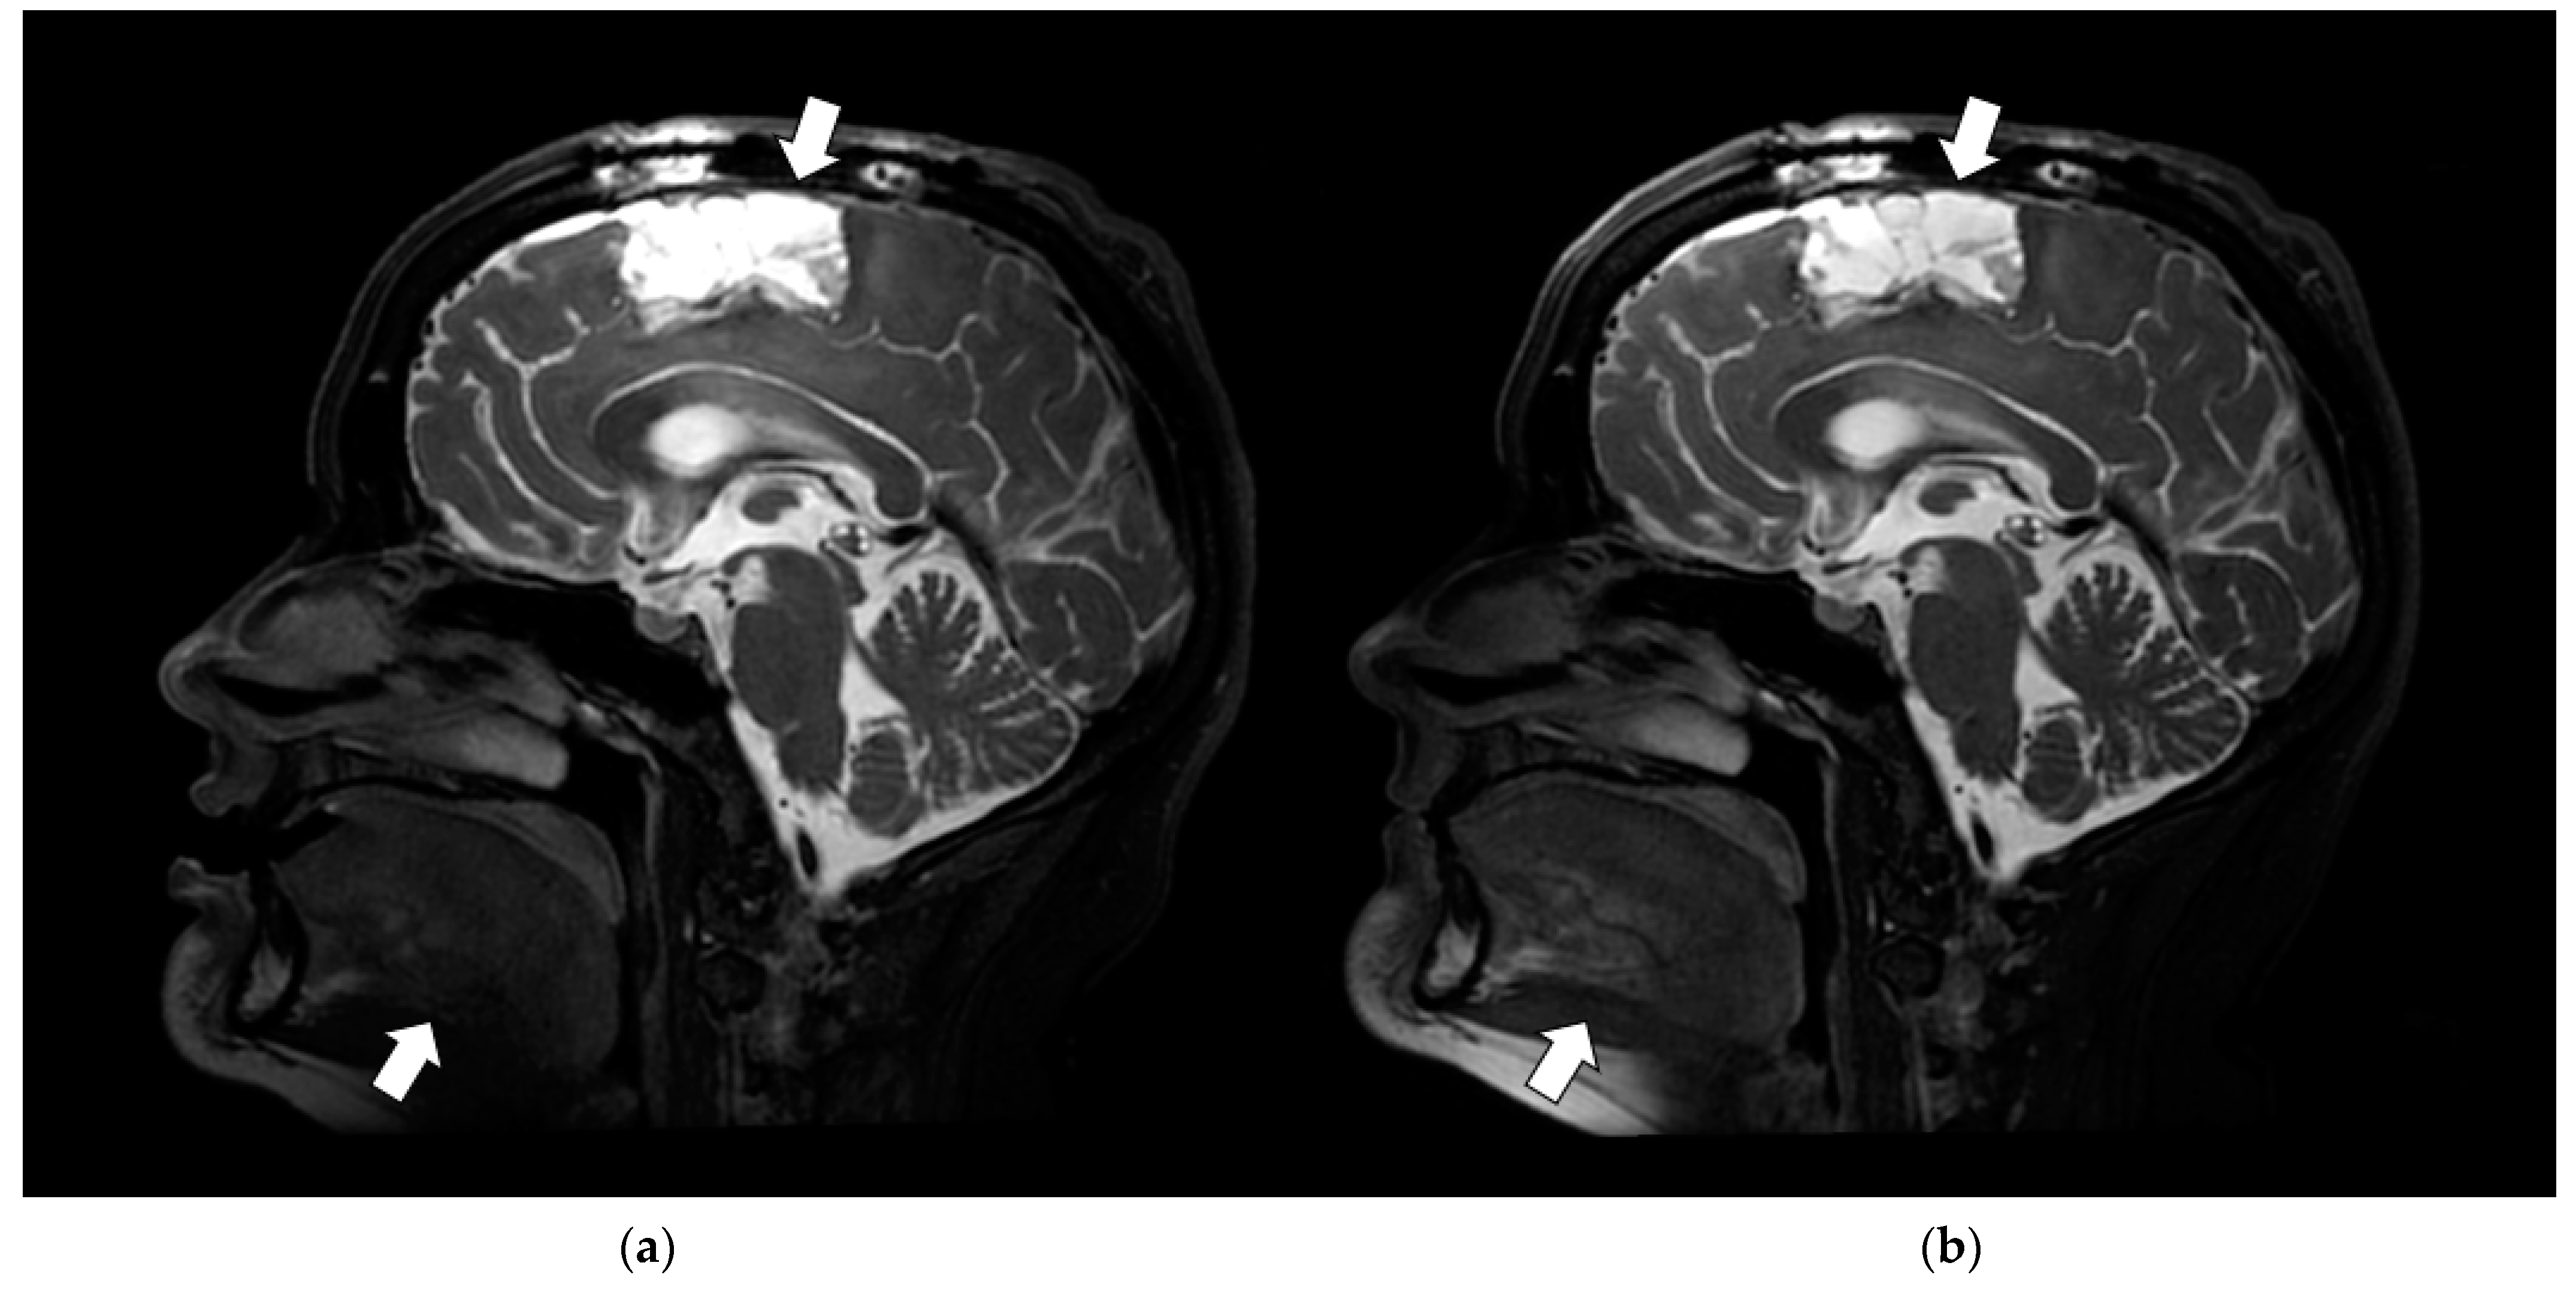

3.3.4. SNR and Anatomic Conspicuity